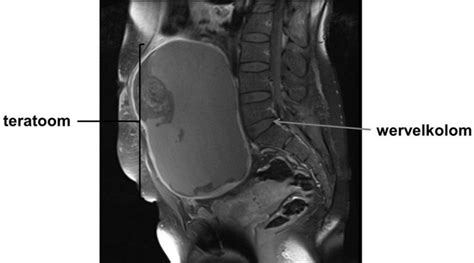

De term teratoom, ook wel 'wondergezwel' of 'monstergezwel' genoemd, verwijst naar een vaak goedaardige tumor die bestaat uit cellen die normaal gesproken niet voorkomen op de plaats waar het gezwel ontstaat. Het is een type tumor dat ontstaat uit stamcellen. Deze cellen kunnen nog veel andere soorten cellen vormen, zoals cellen van het hart en bijvoorbeeld botcellen. Om die reden zitten er vaak allerlei verschillende typen weefsel in het gezwel, zoals huid, haren, botten en tanden. Teratomen zijn meestal goedaardig en komen op verschillende plekken in het lichaam voor. Vaak zitten ze op de eierstokken of teelballen.

Een teratoom (Grieks: τεράτωμα, monsterlijke zwelling) is een vorm van neoplasie, ontstaan uit ongedifferentieerde stamcellen. Het zijn tumoren die weefsels of orgaancomponenten bevatten uit alle drie de kiembladen. Meestal liggen dergelijke tumoren ingekapseld in het lichaam en zijn er verschillende gedifferentieerde weefsels aanwezig, als haar, huid, tanden, spieren en zenuwen. Als het teratoom weefsels uit alle kiembladen bevat, wordt het matuur of rijp genoemd. Een embryonaal (immatuur, onrijp) teratoom daarentegen bevat slecht gedifferentieerde epitheliale en mesenchymatische weefsels. Voor het overgrote deel zijn teratomen goedaardige tumoren.

Een teratoom is een type tumor dat ontstaat uit stamcellen. Deze cellen kunnen nog veel andere soorten cellen vormen, zoals cellen van het hart en bijvoorbeeld botcellen. Om die reden zitten er vaak allerlei verschillende typen weefsel in het gezwel, zoals huid, haren, botten en tanden. Teratomen zijn meestal goedaardig en komen op verschillende plekken in het lichaam voor. Soms worden ze ook aangetroffen op het stuitje, de neus, rondom de ogen, de nek of middenrif. Afhankelijk van de locatie en de grootte, kan een teratoom klachten veroorzaken. Soms drukken ze op andere organen en dat kan pijn veroorzaken of naarmate ze groter worden, kan je ze voelen.

Sacrococcygeaal Teratoom (SCT)

Een sacrococcygeaal teratoom (SCT) kan geheel intrapelvien gelegen zijn en is dan uitwendig niet zichtbaar. Zo’n SCT kan zeer aspecifieke symptomen geven. Bij de eerste patiënte, een pasgeboren meisje, werd vóór de geboorte vastgesteld dat zij intrapelvien een cysteuze massa had. Dit was een benigne SCT. Na verwijdering hiervan bleek zij een neurogene blaasdisfunctie te hebben. Bij de tweede patiënt, een 2-jarige jongen, ontstond een maligne SCT na 2 incomplete resecties van een benigne intrapelvien SCT. De twee andere patiënten, een 4- en een 15-jarig meisje, hadden beiden klachten van obstipatie en buikpijn. Ook zij bleken een SCT te hebben. Vroege detectie en radicale excisie, inclusief verwijdering van het os coccygis, zijn nodig om maligne ontaarding te voorkomen. Epidemiologie: 1 op de 15.000 tot 30.000 baby’s heeft deze tumor en in Nederland worden per jaar ongeveer zes kinderen met deze tumor geboren. De tumor komt daarbij vier keer zo vaak voor bij meisjes dan bij jongens. Diagnose: Door een gestructureerde orgaanscreening en verbeteringen in techniek, worden tegenwoordig ongeveer 2/3 van alle SCT al tijdens de zwangerschap vastgesteld. Met name de volledig inwendig gelegen SCT zijn soms lastig tijdens de zwangerschap vast te stellen en komen soms pas na de geboorte aan het licht. Als er een SCT tijdens de zwangerschap wordt vastgesteld, betekent dit dat het kind nauwkeurig dient te worden opgevolgd. Dit zal met herhaaldelijke echo onderzoeken gebeuren. Hierbij wordt gekeken hoe snel de tumor groeit en of het kind hiervan problemen ervaart. De baby moet namelijk naast zijn eigen lichaam ook de tumor met bloed voorzien en dit kan een grote belasting voor het hart vormen met kans op het ontwikkelen van hartfalen. Zoals gezegd is het SCT in de meerderheid van de gevallen een goedaardige tumor, een kwaadaardige tumor bij de geboorte wordt maar in ongeveer 7% van alle gevallen gezien. Echter, de tumor kan snel kwaadaardig worden, waardoor een snelle operatieve behandeling in alle gevallen noodzakelijk is. De behandeling: Alle SCT moeten middels een operatie worden verwijderd, onafhankelijk of ze goed- of kwaadaardig zijn. Doordat de doorbloeding van de tumor zeer goed is, is dit voor het hart van het kind een extra belasting. Daarnaast bestaat het risico op een bloeding vanuit de tumor die zeer ernstig kan zijn. Op basis van deze redenen worden kinderen met een SCT altijd vrij snel na de geboorte geopereerd, waarbij de tumor in zijn geheel weggenomen wordt samen met het botje van het stuitbeen. Bij kinderen met een bloeding of waar tijdens de zwangerschap reeds hartfalen is vastgesteld, moet een spoedoperatie direct na de geboorte plaatsvinden. De kinderchirurg neemt met de ouder(s) de operatie en het postoperatieve beloop door en bespreekt samen eventuele vragen. De kinderanesthesist legt alle details over de narcose uit. Opvang na de geboorte: Kinderen met een SCT worden in een academisch ziekenhuis met kinderchirurgische afdeling en een neonatale intensive care unit (NICU) geboren of worden hiernaartoe overgeplaatst als het van te voren niet bekend was. In principe is een keizersnede niet per se noodzakelijk; dit zal individueel worden bepaald en hangt onder andere van het verloop van de zwangerschap af. Op de NICU is het mogelijk nodig om het kind te helpen de bloeddruk op pijl te houden met medicatie en mogelijk moet het ook worden beademd. Soms is er geen ondersteuning nodig. Dit hangt onder andere samen met de leeftijd waarop het kind wordt geboren en hoe de zwangerschap tot de geboorte is verlopen. Na de operatie: Na de operatie wordt het kind teruggebracht naar de NICU voor verdere observatie. Soms is het noodzakelijk dat het kind nog wordt beademd en nog niet direct uit de narcose wakker wordt gemaakt. Het kind kan na de operatie gewoon worden gevoed, maar de hoeveelheid zal langzaam worden opgebouwd. De wond dient de eerste dagen goed in de gaten te worden gehouden, omdat er in dit gebied makkelijk wondontstekingen kunnen ontstaan. Afhankelijk van de uitbreiding van de tumor in de buik wordt er ook nog een echo van de nieren en heupgewrichten gemaakt om te kijken of deze door de tumordruk zijn beschadigd. Als het weefselonderzoek toont dat er sprake is van een kwaadaardige tumor, kan het nodig zijn dat het kind chemotherapie moet ondergaan. Risico’s van de operatie: Het grootste risico tijdens een operatie is een bloeding van de tumor zelf of de vaten die de tumor van bloed voorzien. Om dit te voorkomen kan het nodig zijn om eerst met een kijkoperatie de verzorgende bloedvaten te onderbinden voordat dan in buikligging via de bil de tumor wordt verwijderd. Soms kan ook direct vanuit deze positie de verzorgende bloedvaten onderbonden worden alvorens de tumor wordt verwijderd. Verwachtingen op de lange termijn: In ongeveer 9 tot 18% van de gevallen kan het SCT weer terugkomen; meestal is dit binnen drie jaar na de operatie. Daarom worden kinderen die zijn behandeld ook nauwkeurig opgevolgd met een regelmatige policontrole, in het begin om de drie maanden. Hierbij wordt het kind onderzocht en wordt bloed afgenomen. Indien nodig kan ook een echo of een MRI scan worden gemaakt. De kinderchirurg bespreekt dit samen met de ouder(s). Tijdens de zwangerschap wordt de bekkenbodem van het kind in wisselende mate door de tumor verdrongen. Hierdoor kunnen later poep- en plasklachten ontstaan. De ernst van de klachten en de invloed op de levenskwaliteit is heel wisselend en niet alle kinderen ontwikkelen deze klachten.